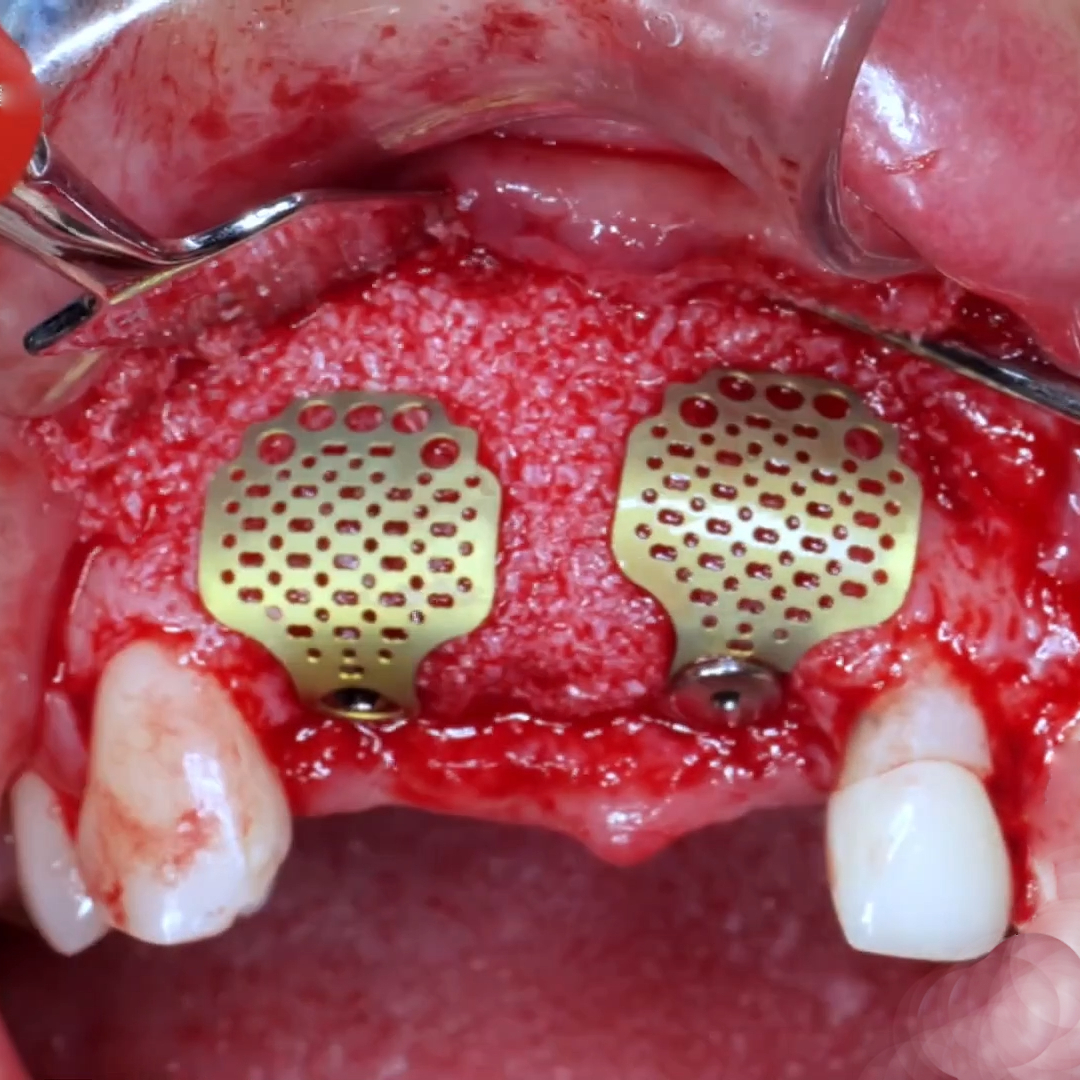

Our Titanium Mesh Membrane is designed to offer optimal support in guided bone regeneration (GBR) procedures, combining structural stability with excellent adaptability. The ultra-thin, anatomically contoured design allows for a comfortable fit and easy surgical handling, while maintaining strong support for the defect area. It can be easily trimmed and shaped to match various bone contours, making it a reliable and versatile choice in both simple and complex cases.

Enhanced fixation: Designed to be used with bone tacks for stable placement

Perforated (lightening) holes: Ensure good vascularization and promote blood supply to the regeneration site